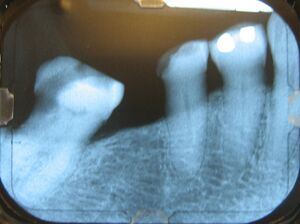

Alveolar bone loss

Bone is lost through the process of resorption which involves osteoclasts breaking down the hard tissue of bone. A key indication of resorption is when scalloped erosion occurs. This is also known as Howship's lacuna.[18] The resorption phase lasts as long as the lifespan of the osteoclast which is around 8 to 10 days. After this resorption phase, the osteoclast can continue resorbing surfaces in another cycle or carry out apoptosis. A repair phase follows the resorption phase which lasts over 3 months. In patients with periodontal disease, inflammation lasts longer and during the repair phase, resorption may override any bone formation. This results in a net loss of alveolar bone.[19]

Alveolar bone loss is closely associated with periodontal disease. Periodontal disease involves the inflammation of the gingiva or gums or gingivitis. Studies in osteoimmunology have proposed 2 models for alveolar bone loss. One model states that inflammation is triggered by a periodontal pathogen which activates the acquired immune system to inhibit bone coupling by limiting new bone formation after resorption.[20] Another model states that cytokinesis may inhibit the differentiation of osteoblasts from their precursors, therefore limiting bone formation. This results in a net loss of alveolar bone.[21]

The density of the alveolar bone in a given area also determines the route that dental infection takes with abscess formation, as well as the efficacy of local infiltration during the use of local anesthesia. In addition, the differences in alveolar process density determine the easiest and most convenient areas of bony fracture to be used, if needed during tooth extraction of impacted teeth. During chronic periodontal disease that has affected the periodontium (periodontitis), localized bone tissue is also lost. The radiographic integrity of the lamina dura is important in detecting pathologic lesions. It appears uniformly radiopaque (or lighter).[24]